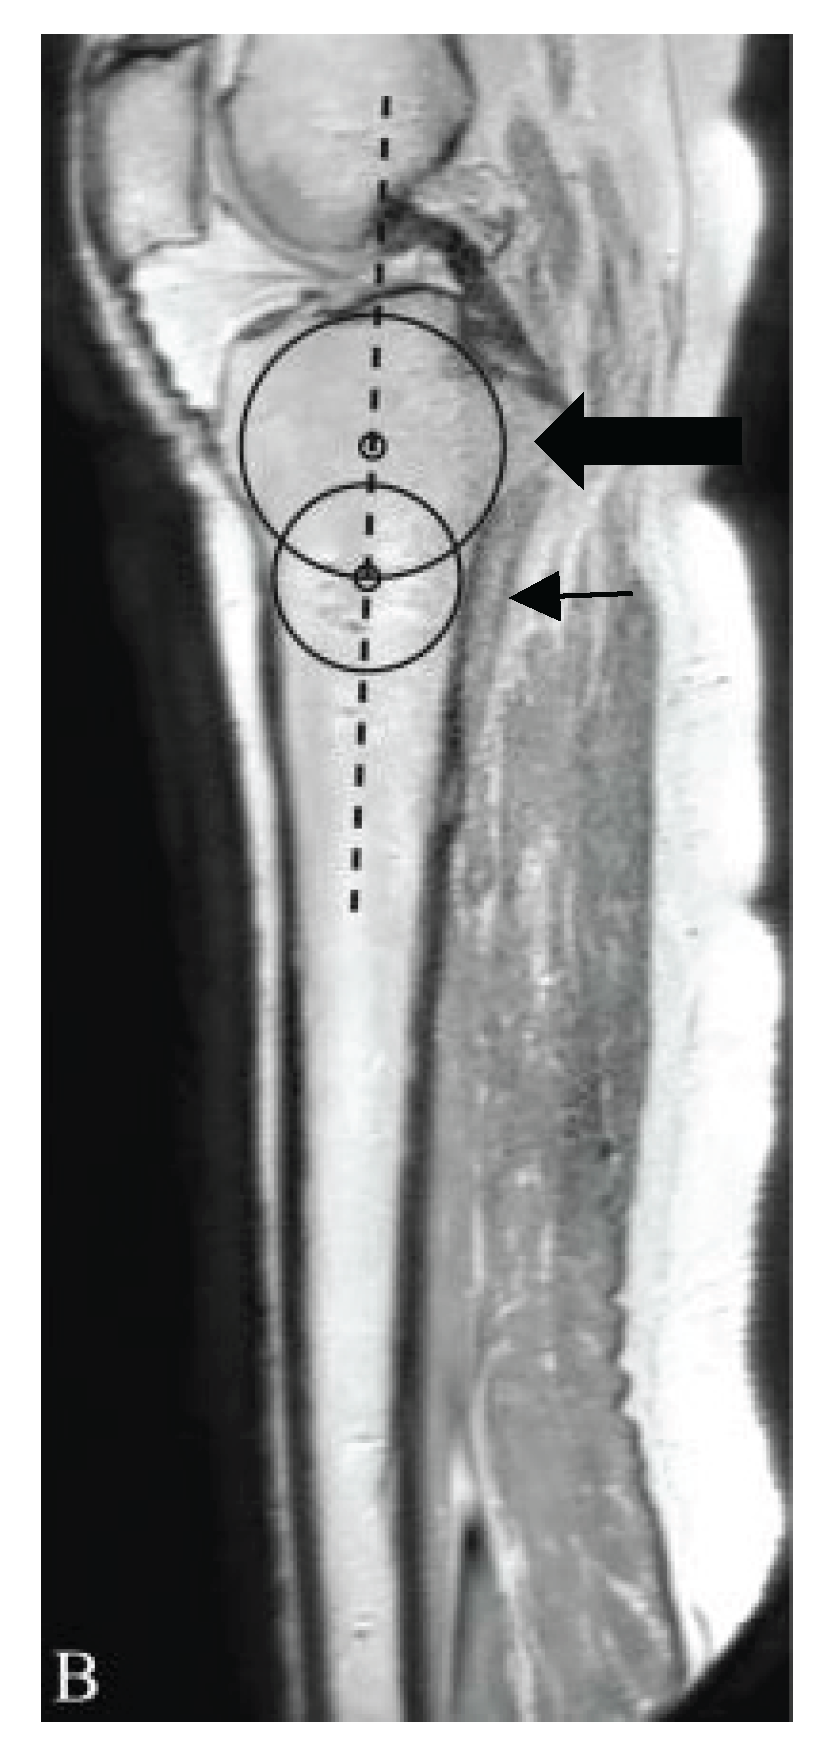

Measurement of Lateral Posterior Tibial Slope

- Hudek R, Schmutz S, Regenfelder F, Fuchs B, Koch PP. Novel Measurement Technique of the Tibial Slope on Conventional MRI. Clin Orthop Relat Res. 2009;467(8):2066. [CrossRef]